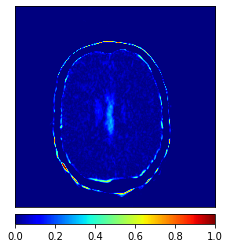

In this paper, we propose a bidirectional learning model, known as dual contrast cycleGAN (DC-cycleGAN), for medical image synthesis from unpaired data. Specifically, a dual contrast (DC) loss is formulated that leverages the advantage of samples from the source domain as negative samples to indirectly build constraints between real source and synthetic images via discriminators, and synthesize images more related to the target domain by enforcing the synthetic images to fall far away from the source domain. In addition, structural similarity index (SSIM) [35] and cross-entropy (CE) [48] are integrated into the DC-cycleGAN structure to avoid disappearing gradient information that is caused by a mean absolute error (MAE) and synthesizing irrelevant images. SSIM considers luminance [35] and CE converges fast as its back-propagation error is less than MSE [28]. As can be seen in Figs. 1 and 2, using SSIM and CE with dual contrast can generate more clear and accurate MR images as compared with that of MAE and MSE, and SSIM and CE without dual contrast loss. Although both SSIM and CE with dual contrast and without dual contrast generate similar CT images, SSIM and CE with dual contrast quantitatively generate better images as shown in Table 4. The experimental results indicate that DC-cycleGAN is able to consider more complex features such as structure in synthesizing images and produce remarkable results as compared with other state-of-the-art methods reported in the literature.

Moreover, Figs. 6 and 7 show the synthesized MR and CT images along with the errors between the real and synthesized images by different methods, respectively. It can be seen that the synthesized images by DC-cycleGAN are more identical to the real ones as compared with other methods. This indicates that effectiveness of SSIM and CE along with dual contrast in synthesizing images. In addition, the error between the groundtruth and synthesized MR/CT images by DC-cycleGAN is relatively less as compared with other methods.

Tables 3 and 4 show the results of MR and CT synthesis, respectively. As can be seen, all components play vital role in both tables. SSIM & CE (w) performs significantly better than other losses in synthesizing MR images. This also can be seen visually in Fig. 1. In contrast, SSIM&CE (w) performs slightly better than SSIM&CE (wo) in synthesizing CT images, both generate more or less similar CT images (see Table 4).